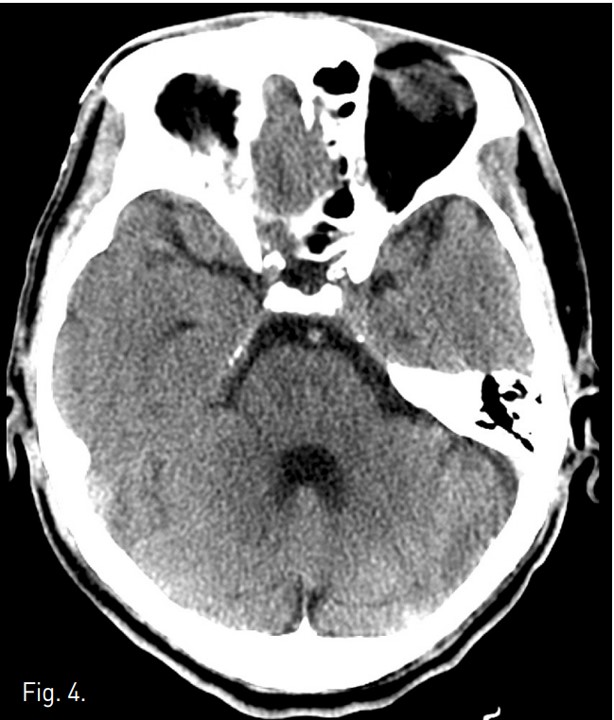

TACE 시술 4시간 후 좌측 상하지의 motor weakness와 감각 이상이 발생하였고 신경학적 검사 상 좌즉 hemiparesis와 abnormal gait pattern소견 보였음. 9시간 후 brain CT 에서 parenchymal lipiodol uptake와 같은 이상소견 발견되지 않았으나(Fig. 4), brain MRI 확산강조영상에서 상부 교뇌 우뇌 paramedian aspect와 우측 소뇌, 양측 대뇌 반구에 다발성 뇌혈관 색전증 소견이 보였음(Fig. 5). 3일 후 시행한 경식도 초음파와 contrast echocardio graphy 에서 난원공 개존 (patent foramen ovale)와 이에 의한 우좌 단락이 관찰되었음. Heparin 항응고요법 후 aspirin을 지속적으로 복용하였고, 2개월 간 재활 치료를 받은 다음 지팡이를 짚으면서 정상 보행이 가능해짐.

Fig. 4.

Fig. 4. Pre-contrast brain CT scan at the level of the upper pons demonstrates no abnormality.